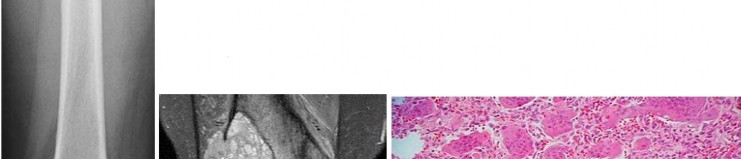

A 15-year-old male presents with deep knee pain awakening him at night. Radiographs show a permeative destructive lesion in the distal femoral metaphysis with a 'sunburst' periosteal reaction and Codman's triangle.

Biopsy confirms high-grade conventional osteosarcoma. What is the most critical prognostic factor for long-term overall survival in this patient?

Explanation

For localized high-grade osteosarcoma, the most important prognostic indicator is the histologic response to neoadjuvant chemotherapy. This is evaluated during the definitive resection. A 'good response' is typically defined as greater than 90% or 99% tumor necrosis. Patients who achieve this level of necrosis have a significantly improved disease-free and overall survival rate compared to 'poor responders' who have extensive viable tumor cells remaining.